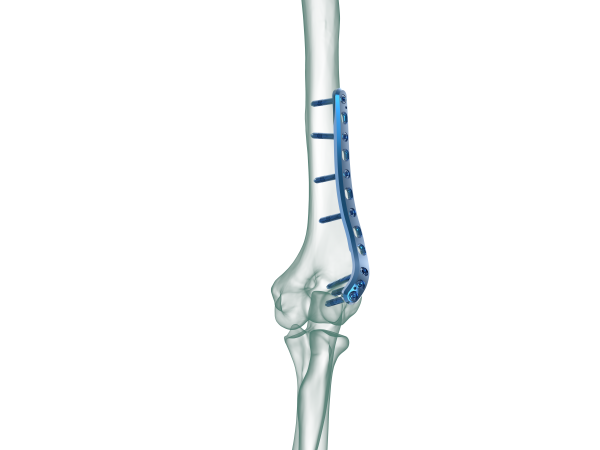

TRUE LOCK Distal Humerus Lateral Anatomic Plate

Anatomical plate; right & left

TRUE LOCK Distal Humerus Lateral Anatomic Plates are precontoured for anatomic fit. No need to bend during the surgery.